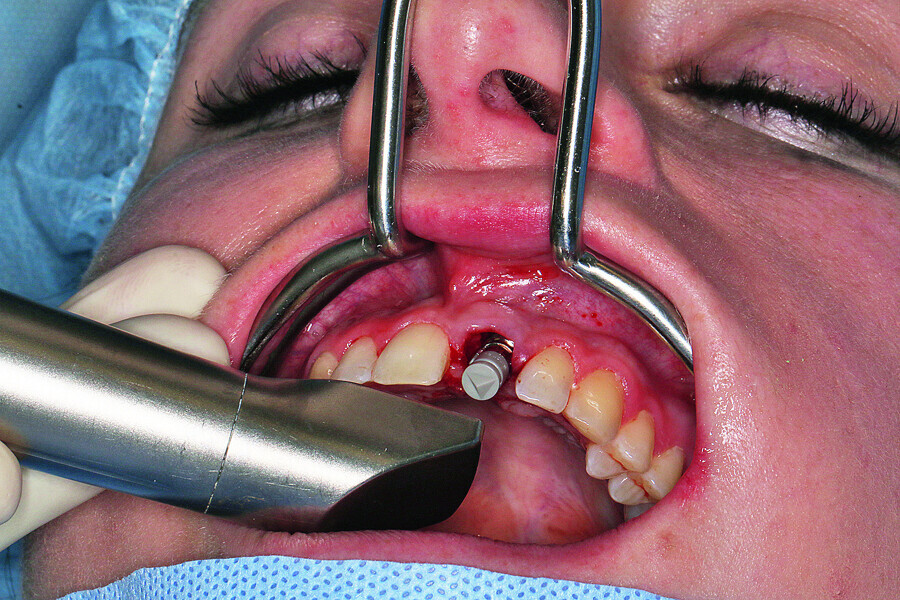

Fig. 9: Preparing the implant bed according to the recommended drill sequence, insertion of the implant using the SICAT surgical guide.